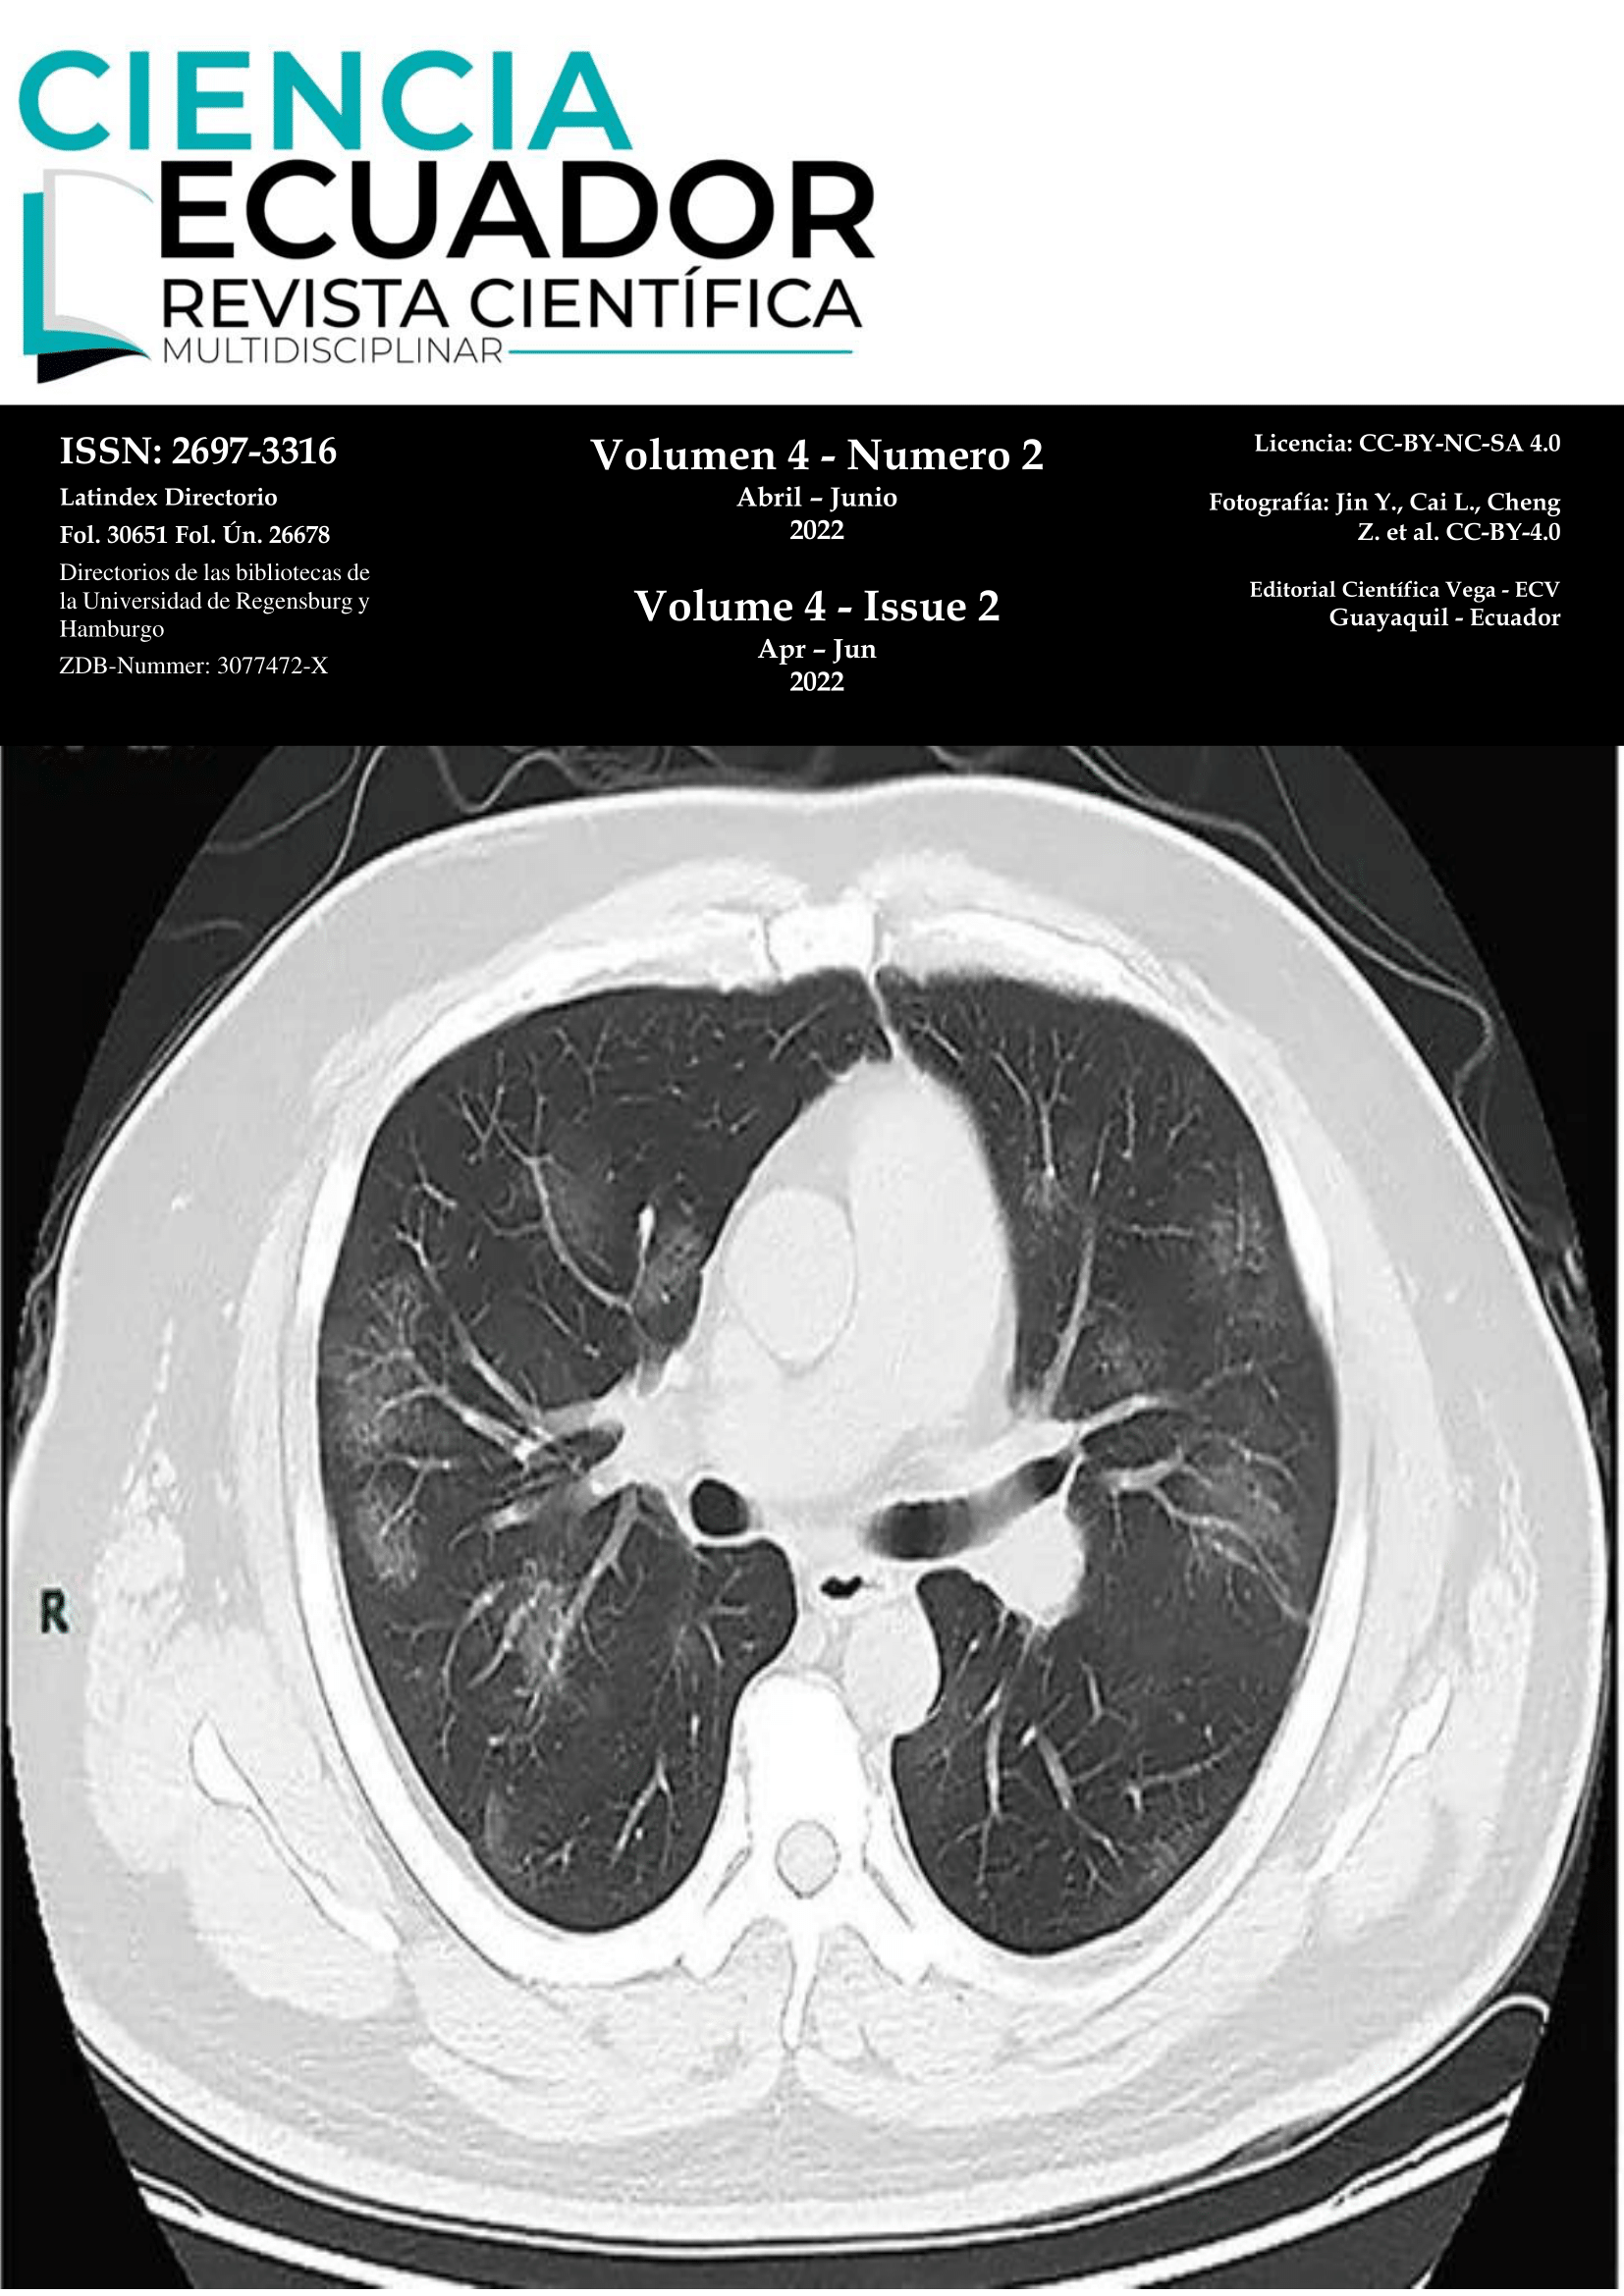

La enfermedad del coronavirus 2019 (COVID-19) puede ocasionar una amplia variedad de complicaciones, algunas de ellas con serias consecuencias, que en ocasiones comprometen la vida del paciente. En cierto grupo de pacientes críticos se ha identificado un estado de hipercoagulabilidad, y en un grupo más pequeño, se ha observado un compromiso de las extremidades debido a isquemia distal. Se presenta el caso de un paciente crítico, con COVID-19, que desarrolló isquemia distal en tres extremidades mientras estuvo hospitalizado en la sala de cuidados intensivos. Se considera que es importante comprender este tipo de fenómenos, para que a futuro se pueda establecer mejores herramientas diagnósticas y terapéuticas.